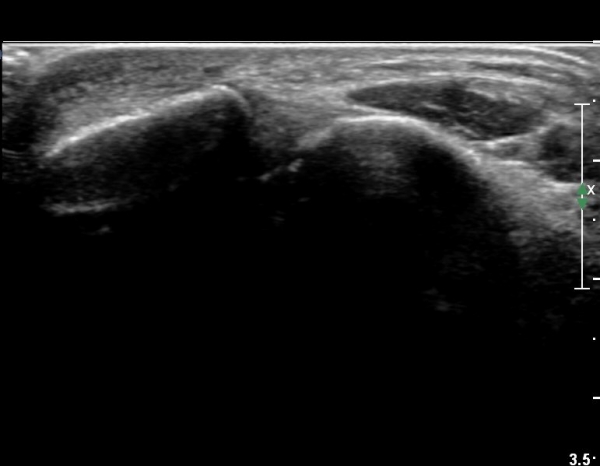

Á¾°ñºñ°ñÀδë Á¾´Ü¸é°Ë»ç¿¡¼­ ÀδëÀÇ ºñ°ñ ºÎÂøºÎ¿¡ Àú¿¡ÄÚ ºÎÁ¾ÀÌ °üÂûµÇ³ª

ºñµî¹æ¼ºÀΰøÀ½¿µ(anisotropic artifact) ¶§¹®¿¡ ÆÄ¿­ÀÌ È®½ÇÄ¡ ¾Ê´Ù(»çÁø 6, 7).

Á¾°ñºñ°ñÀÎ´ë ºÎÇϰ˻翡¼­ ÀδëÆÄ¿­ºÎ ¹ú¾îÁüÀÌ  ¶Ñ·ÈÇÏ´Ù(»çÁø 8).